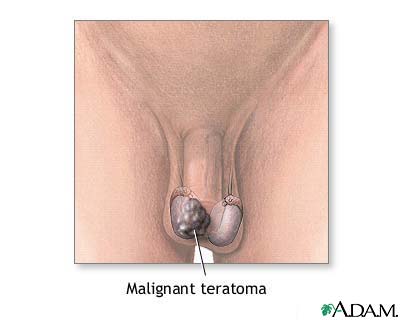

Images